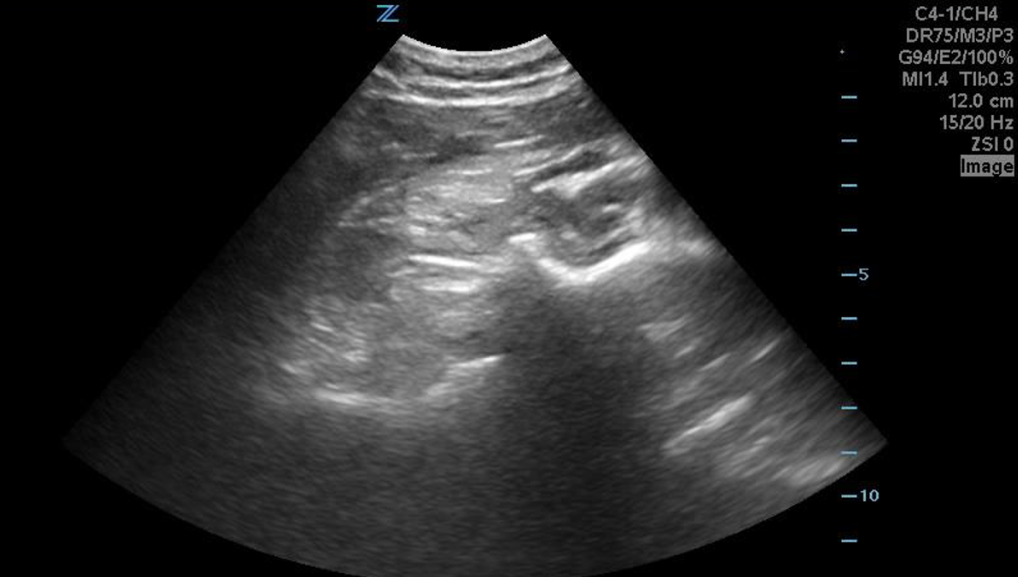

This image was captured by placing the transducer in the long axis, parallel to the scapular spine.

Image 1: Author’s own images and annotations